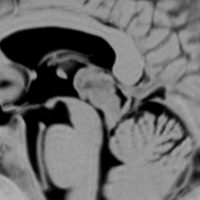

上段のガドリニウム増強MRIでは松果体腫瘍に見えやや境界が不明瞭なので,年齢からはPPTIDが疑われます。しかし,CISSの画像で,中脳上丘との境界がなく中脳腫大があるようにみえ,テクタールグリオーマを疑って経過観察しました。腫瘍がゆっくり増大したので摘出したところPPTIDという診断がつきました。